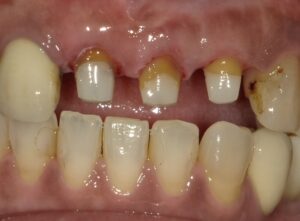

被せ物を被せ終えたところです。

かなりしっかりと治りました。

このように挺出治療によって従来抜歯と言われた

歯も助かることもあります。